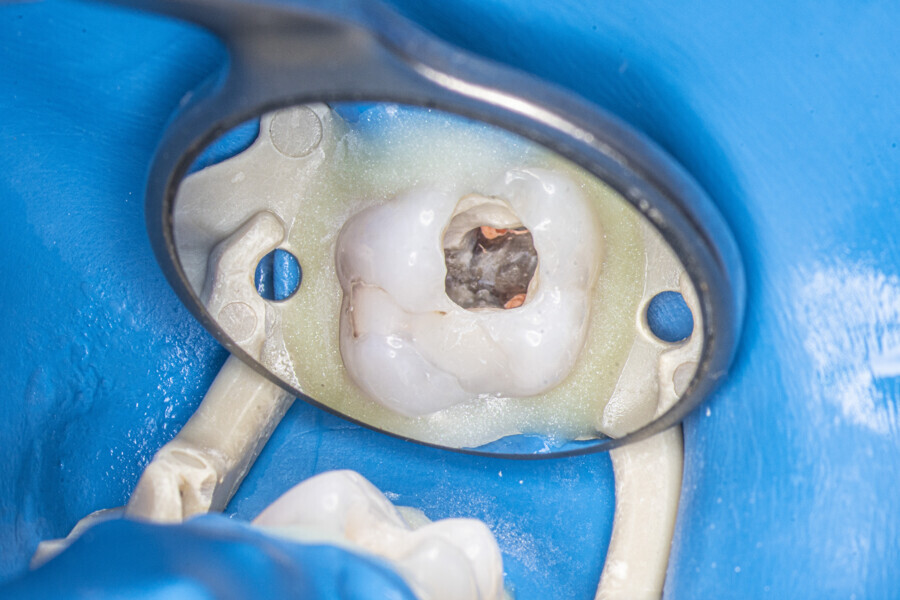

Case 4 (Figs. 47–60)

A 35-year-old female patient was referred to the office owing to the lack of patency in the pulp chamber. The periapical radiograph and CBCT image confirmed that the pulp chamber was completely calcified. The calcification of the pulp chamber was removed with diamond-coated ultrasonic tips. After removing the calcification, four orifices were located and shaped in the sequence described previously. The LPE enhanced irrigation protocol with the SkyPulse laser was performed. In this case, the MB2 canal joined the MB1 canal approximately 4 mm before the apex and was shaped only to this length. Apical preparation and irrigation were performed as described previously. The periapical radiograph revealed that the MB2 canal had a separate apical part, which was cleaned with the irrigants and filled with the sealer, and that the palatal canal had two portals of exit.